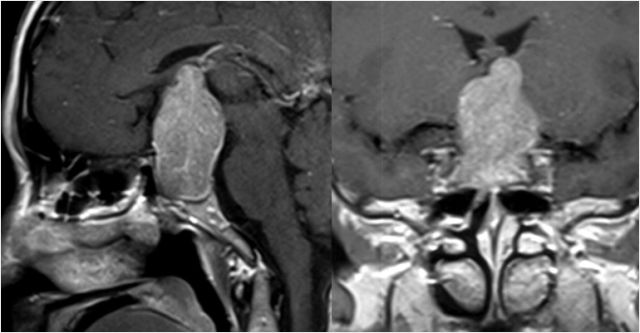

内镜经鼻蝶切除垂体瘤

术前

术后

内镜经鼻蝶切除颅咽管瘤